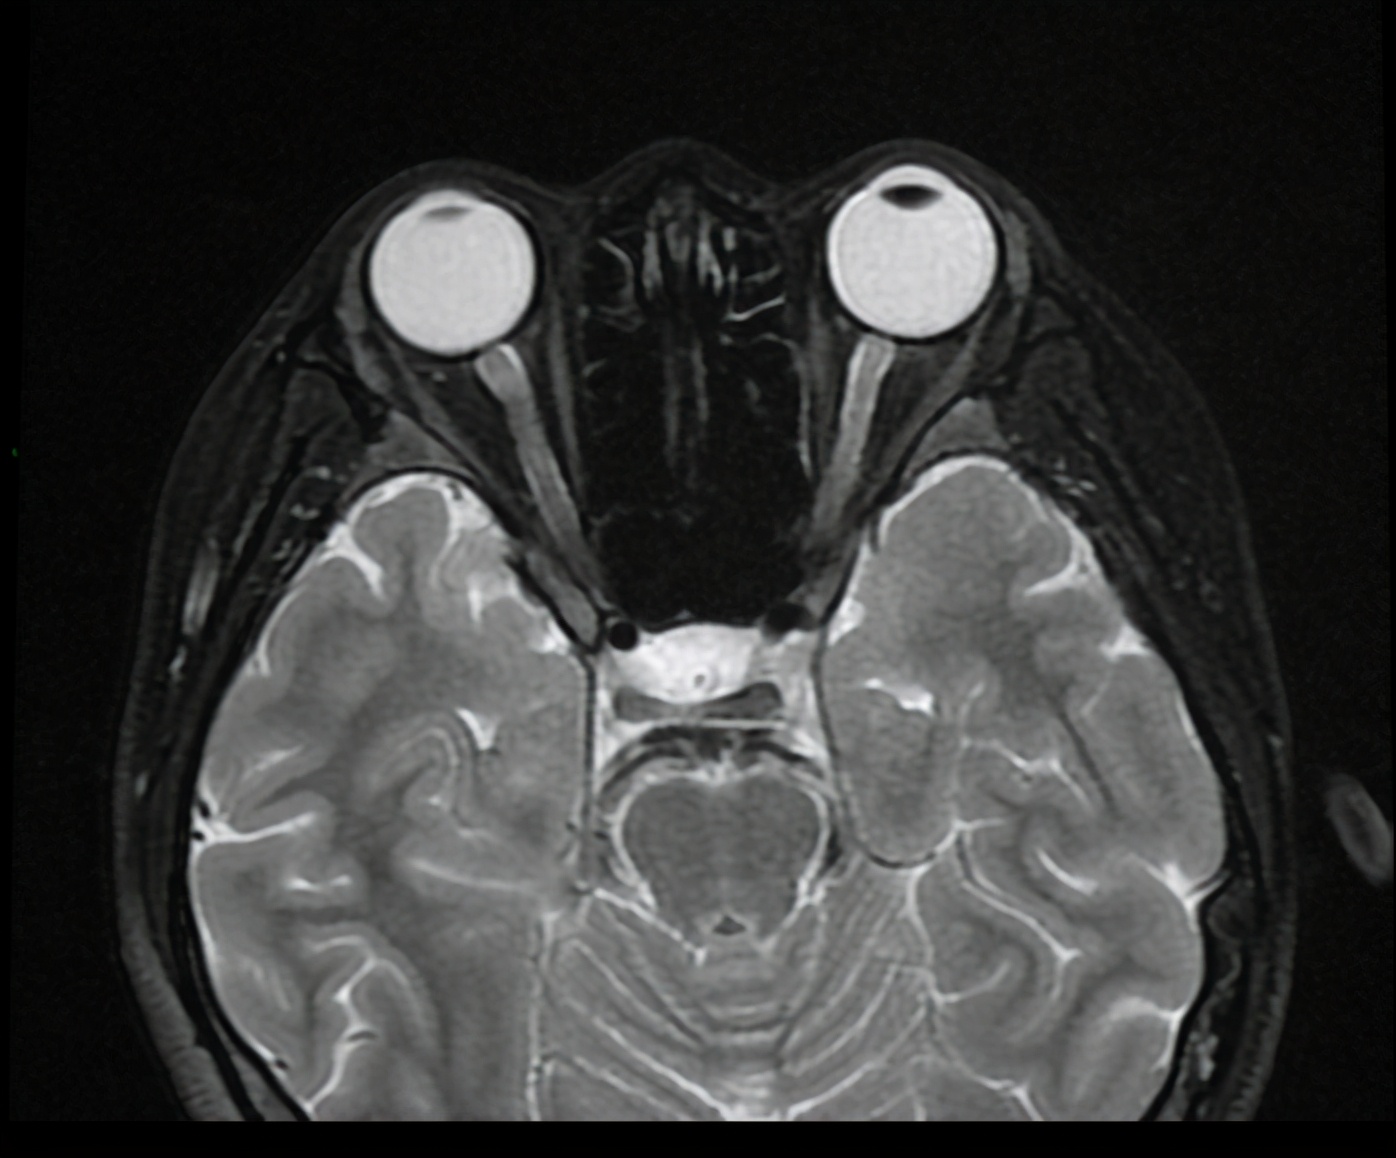

3、眼眶磁共振:双侧视神经鞘膜少量积液,右侧视神经球后段强化明显,考虑炎症性改变可能,双侧桥壁斑片等T1稍长T2信号。

图:眼眶MRI(T2平扫)

MRI提示该患者视神经鞘膜积液、视神经强化。病情进展到此时,似乎我们已经找到了其双目失明的真正原因——视神经病变。那么,现在面临的问题是,前后两次治疗均在同等剂量下进行,患者为何会在第二次治疗中出现视力损害?为何停用异烟肼、乙胺丁醇后视神经的损害迟迟得不到恢复?是停药时间不够,还是患者已出现永久性视神经损害?为何患者双侧视力损害不是同时出现?且双侧视力受损程度不一致?这些都可以用「药物性视神经损害」来解释吗?或者说还有其他原因?带着诸多疑惑,我们再次询问和细致厘清患者起病到病情进展的全过程: